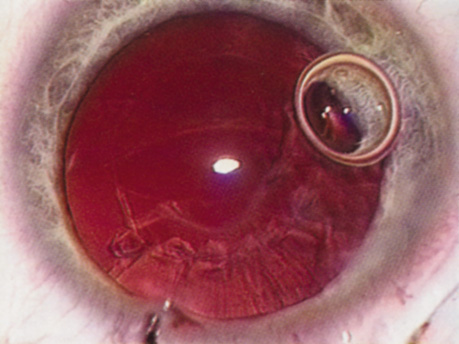

Many patients are most bothered by cataract-induced glare. For these patients, acuity testing under glare situations is indicated. There are several methods to assess visual acuity reduction by glare. The choice of method is often best dictated by the patient's history. If a patient complains of glare problems in the supermarket, or other uniformly illuminated environment, the brightness acuity test can be performed (Mentor Ophthalmics). For this test, the specially illuminated handpiece is held in front of the tested eye using best spectacle correction (Fig. 1). The Snellen acuity is rechecked and can be recorded on each of three light settings.